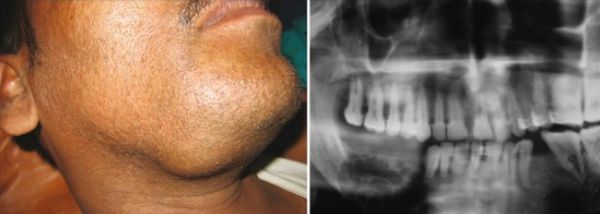

Szkliwiak (ameloblastoma) to łagodny nowotwór rozwijający się z tkanek odpowiedzialnych za tworzenie zębów. Charakteryzuje się powolnym, bezbolesnym wzrostem, dlatego przez długi czas może nie dawać żadnych objawów i pozostawać niezauważony. Najczęściej lokalizuje się w okolicy kąta oraz gałęzi żuchwy.

W miarę powiększania się guza może dojść do deformacji rysów twarzy, przemieszczenia zębów i ich rozchwiania. Mimo znacznych zmian w strukturze kości szkliwiak prawie nigdy nie wywołuje stanów zapalnych, co często utrudnia jego wczesne rozpoznanie.

Szkliwiak najczęściej lokalizuje się w okolicy kąta i gałęzi żuchwy, zwłaszcza w rejonie zębów mądrości. We wczesnym stadium choroba przebiega bezobjawowo, dlatego pacjent przez długi czas może nie zdawać sobie sprawy z obecności guza.

Jest to łagodny nowotwór rozwijający się wewnątrz kości żuchwy. Zazwyczaj rośnie powoli, ale w miarę postępu choroby może prowadzić do rozchwiania i przemieszczenia zębów, zaburzeń zgryzu oraz deformacji twarzy. W bardziej zaawansowanych przypadkach, gdy guz osiąga znaczne rozmiary, dochodzi do widocznego zaburzenia symetrii twarzy, co często wymaga rozległego zabiegu chirurgicznego i długotrwałej rehabilitacji.

- RTG (ortopantomogram) – zdjęcie dwuwymiarowe ukazujące charakterystyczny obraz przypominający „bańki mydlane”, co umożliwia wstępne rozpoznanie szkliwiaka;